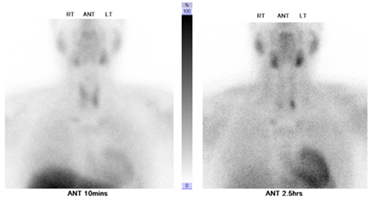

Figure 3 focal mass like lesion in the body of the pancreas with ill-defined outline (size5cm x 3.2cm).

After five months from pancreatic surgery, Patient has been admitted electively after primary hyper parathyrodism localization imaging (Figure 4), to undergo total 4 glands parathyroidectomy and thymoctomy, with half parathyroid gland re implantation in the lower sternothyroid muscle, intraoperative PTH dropped from 236 to 15.5pg/ml, about 90% reduction, post procedure. It was without complication. Follow up Pathology report revealed4 glands hyperplasia.